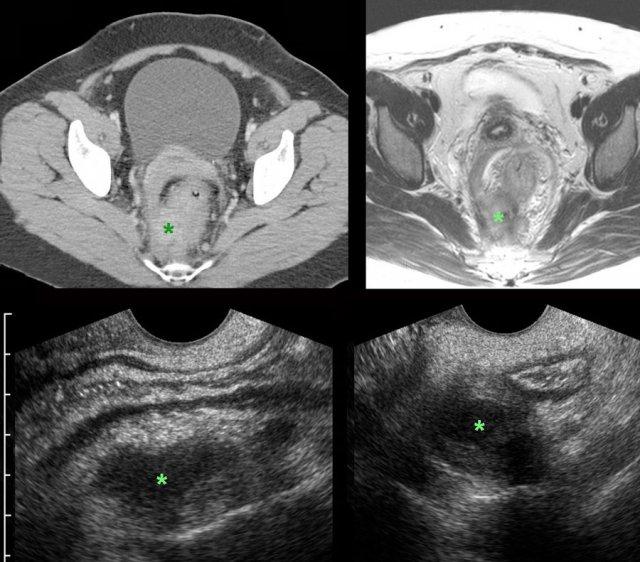

Phân biệt DIE với actinomycosis

Bệnh nhân nữ 43 tuổi với tiền sử đau vùng chậu dưới kéo dài. Trong quá trình siêu âm thường quy (không hiển thị ở đây), phát hiện dày thành trực tràng không đối xứng không rõ nguyên nhân kèm viêm mô mỡ xung quanh. Chỉ định chụp CT.

Hình ảnh

CT và MRI tiếp theo xác nhận các phát hiện trên siêu âm và còn cho thấy sự lan rộng của các bất thường đến mạc cạnh trực tràng và cổ tử cung.

Trong khối (*) có thể thấy các vùng hoại tử hoặc dịch nhỏ.

CRP là 2.

TVUS cho thấy dày thành trực tràng do phù nề với hình thái trực tràng còn lại bình thường, và một khối giảm âm không điển hình (*) ở phía sau bên phải, được bao quanh bởi mô mỡ tăng âm không thể nén ép.

Khối cảm giác rất cứng khi thăm khám. Chẩn đoán gợi ý là một thể DIE không điển hình.

Cuối cùng, sinh thiết qua nội soi đại tràng dưới hướng dẫn siêu âm nội soi (EUS) sâu cho thấy nhiễm trùng xơ hóa mức độ thấp, không có đặc điểm của lạc nội mạc tử cung hay ác tính. Chẩn đoán actinomycosis được đặt ra. Sau sáu tháng điều trị penicillin tĩnh mạch (qua port-a-cath), chỉ còn lại các bất thường tồn dư tối thiểu. Bệnh nhân hết đau. Mười lăm năm trước, bệnh nhân đã được tháo dụng cụ tử cung (IUD). CRP thấp phù hợp với nhiễm trùng mạn tính mức độ thấp kéo dài. Không có bằng chứng vi khuẩn học.